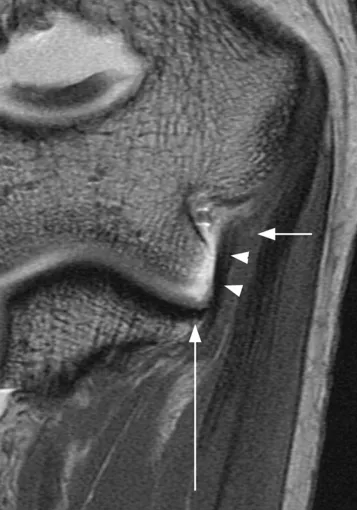

滑膜皱襞

后外侧滑膜皱襞,是关节滑膜增生折叠形成的结构,过度增生或损伤时可能引发关节不适。

(a)33 岁女性受试者的矢状位 T2 加权磁共振成像,以及(b)对应的示意图,清晰显示出后外侧滑膜皱襞的前后径(白色箭头所示)与头尾径(黑色箭头所示)。图中 AM 代表肘肌。

(c)与图 a 相同的磁共振影像,以及(d)对应的示意图,显示出肱骨小头的假性缺损(箭头所示),及其与后外侧滑膜皱襞的密切关联。图中 AM 代表肘肌。

(e)同一志愿者的冠状位三维稳态进动快速成像磁共振影像,以及(f)对应的示意图,显示出后外侧滑膜皱襞的外侧部分(箭头所示)。图中 CET 代表共同伸肌腱,ED 代表指伸肌,SM 代表旋后肌。